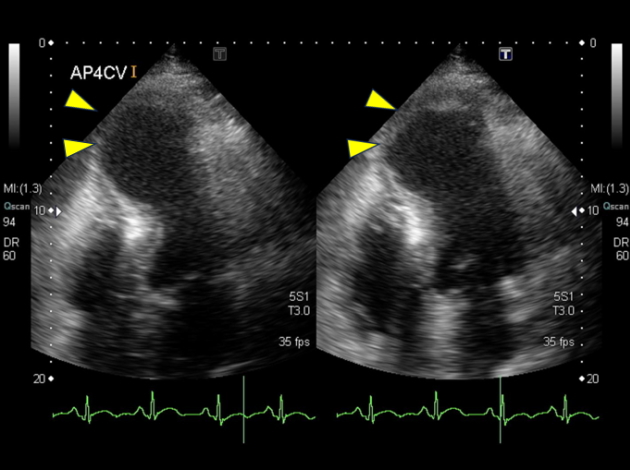

心筋梗塞による心室瘤